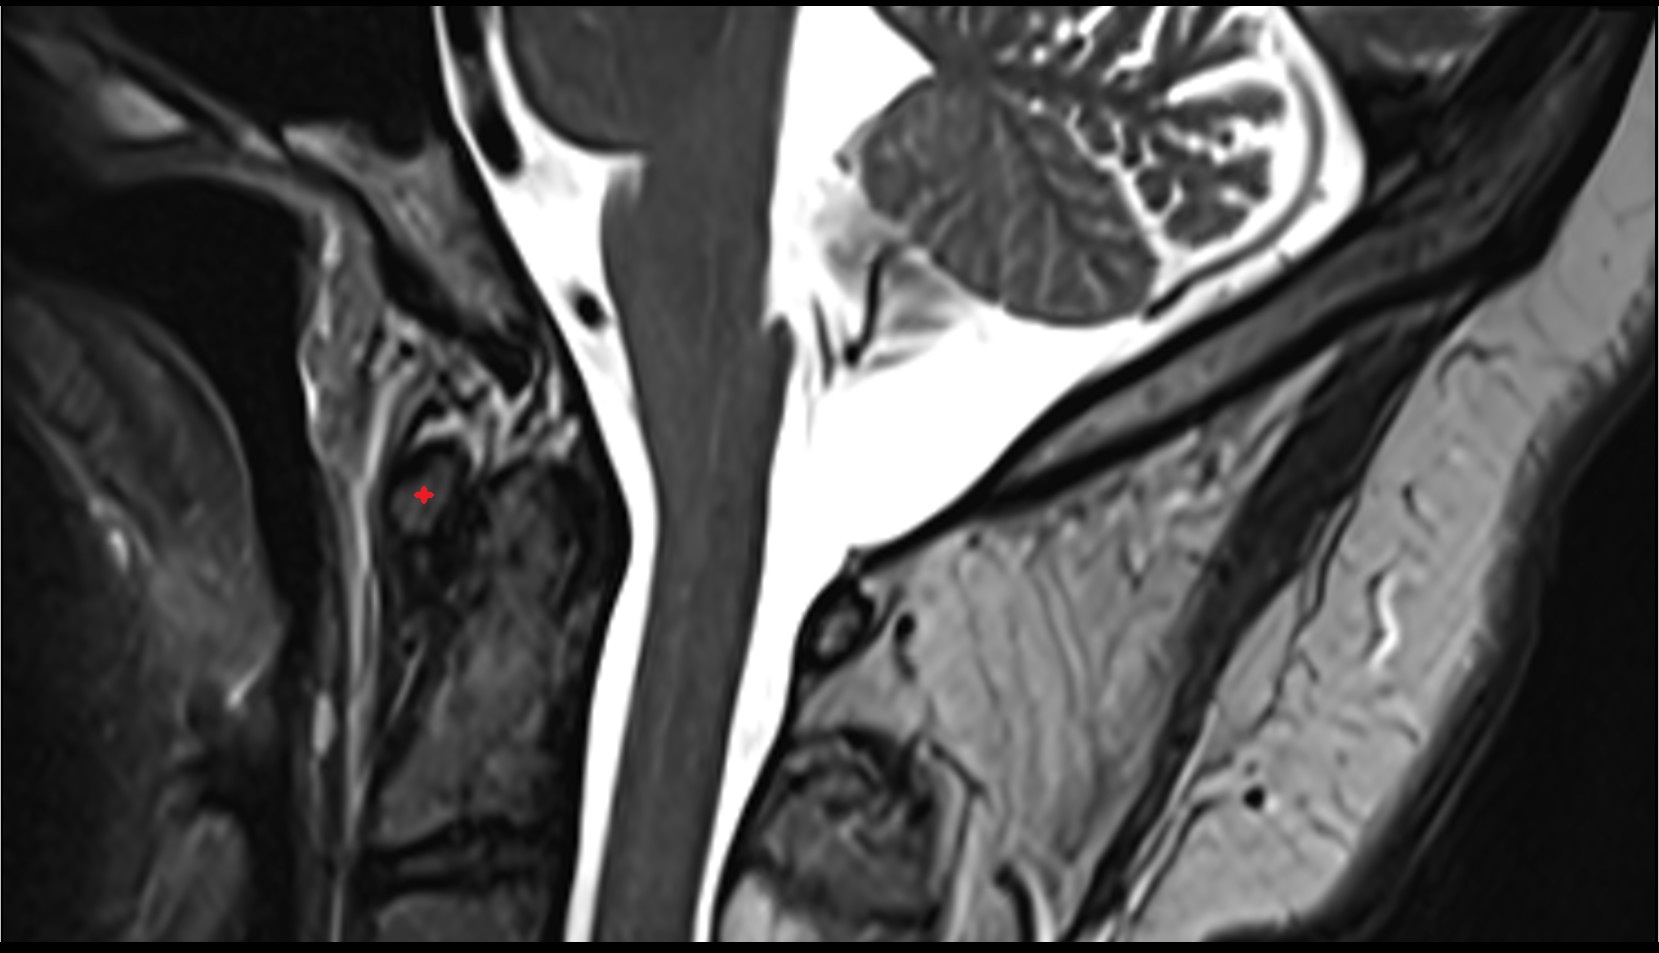

- Uterus

- Body of uterus

- Fundus of uterus

- Cervix of uterus

- Isthmus of uterus

- Vagina

- Fornix of the vagina

- Endometrium of uterus

- Myometrium of uterus

- Perimetrium of uterus

- Junctional zone of uterus